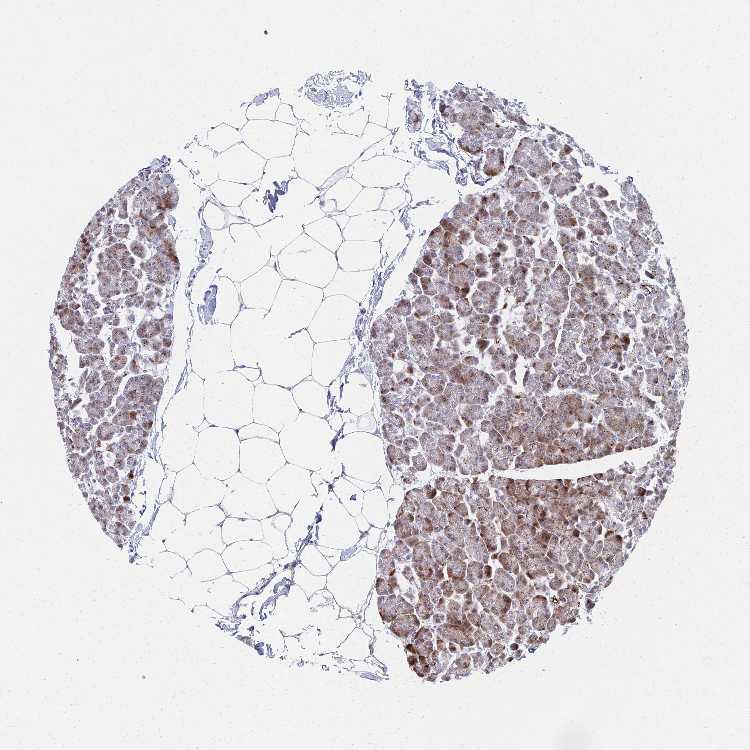

Antibody HPA057771

Exocrine glandular cells High

Pancreatic endocrine cells Low